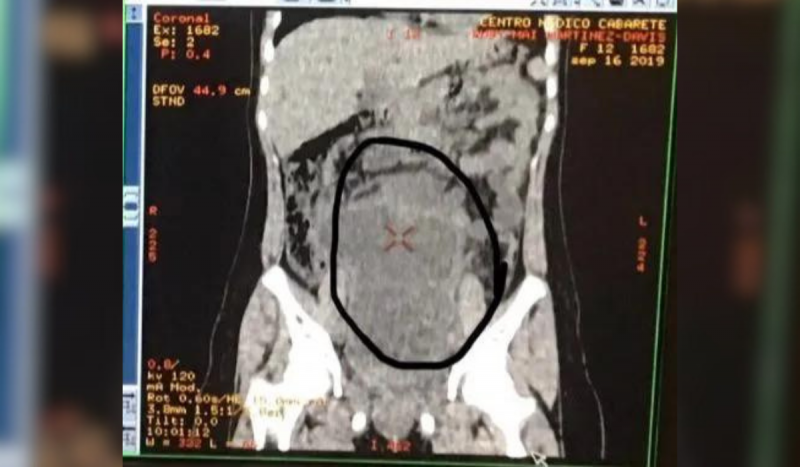

Exame de raio-x mostra abdômen de paciente que tinha tumor com cabelos, dentes e ossosExame de imagem mostrou tumor gigante no estômago de menina de 12 anos – Foto: SWNS/The Sun/Reprodução/ND

Uma adolescente, de 12 anos, precisou fazer uma cirurgia após dar entrada no hospital com fortes dores abdominais. Os médicos precisaram extrair um tumor com cabelos, dentes e ossos do estômago da paciente.

Após os médicos examinarem Ruby, foi identificado um tipo de tumor raro de células germinativas conhecido como teratoma – em geral, é comum que se apresente um tumor com cabelos, dentes e ossos.

Mesmo não sendo maligno, o tumor com cabelos, dentes e ossos atingiu um tamanho tão grande que provocou o rompimento do apêndice da menina.

O item, segundo os médicos, pesava o equivalente a um bebê recém nascido, cerca de 3,63 kg.